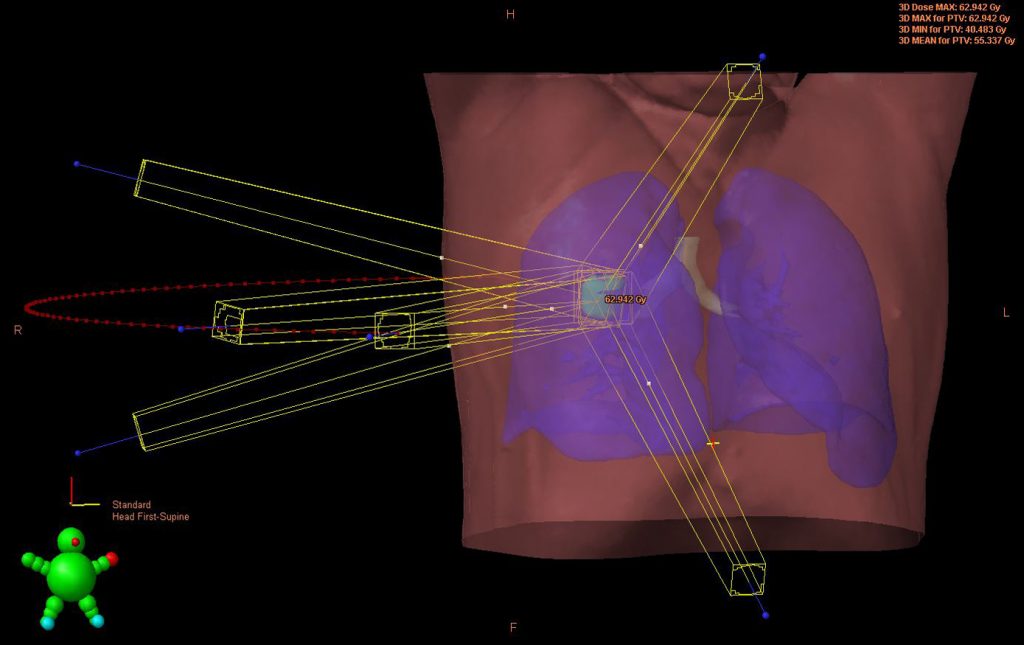

Stereotaktische Bestrahlung am Kopf und Körper

Eine Sonderform der perkutanen Radiotherapie stellt die stereotaktische Bestrahlung von z. B. solitären oder zahlenmäßig geringen […]